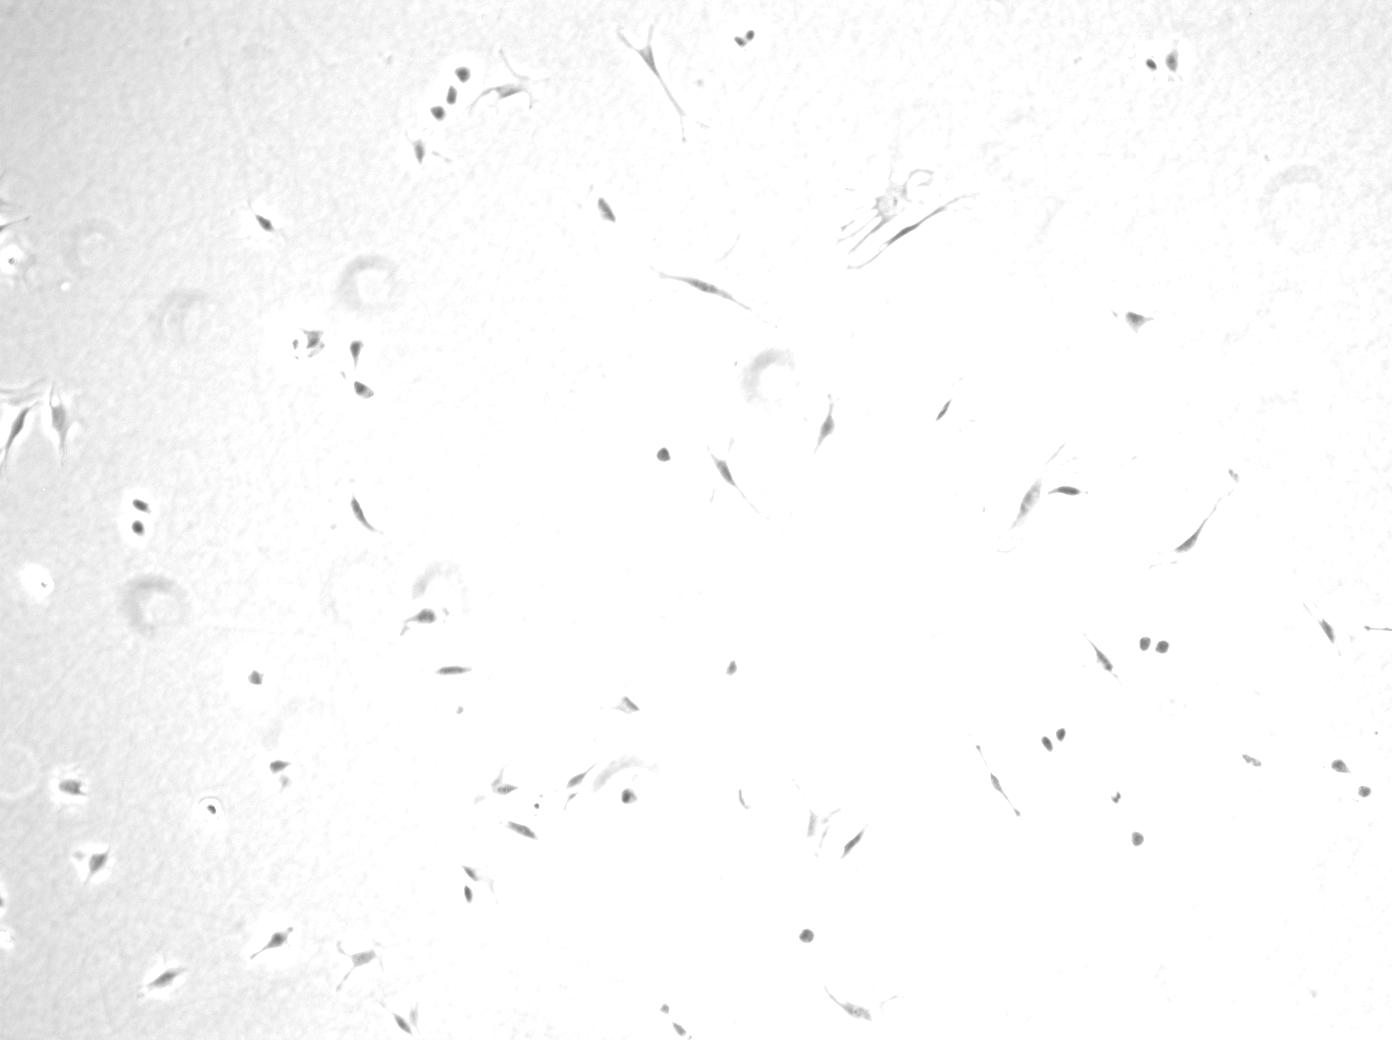

The database applied in [23] consists of two different types of cells: bovine aortic endothelial cells and C2C12 muscle stem cells ,which is available at http://www.albany.edu/celltracking/downloads.html. Each type of cell has 10 training images and 10 testing images. The average number of cells in bovine aortic endothelial cells images and C2C12 muscle stem cells images are 4,900 and 9,800, respectively. We show two samples from this data as in Fig. 3. The database used in [41, 49, 50, 44, 42] contains three different kind of cells images, which are bovine aortic endothelial cells, C2C12 stem cells and muscle stem cells, which is available at http://www.albany.edu/celltracking/downloads.html. The detail specifications are presented in Table 1, and some sample images are shown in Fig. 6. Li et al. created a dataset [22, 32] contains two image sequences of MG-63 osteosarcoma cells with 150 frames and another two sequences of proprietary amnion epithelial stem cells with 256 frames. In [47, 51], cell images are obtained in six different exposure durations( [50 100 200 300 400 500]ms) for three different cell dishes, as shown in Fig. 4. The cell database from BU-BIL [7] contains 235 images in total and 152 are phase contrast images, which 35 rat smooth muscles cells, 70 rabbit smooth muscle cells, and 47 fibroblasts, which is available at http://www.cs.bu.edu/∼betke/BiomedicalImageSegmentation. We show some samples in Fig. 5.